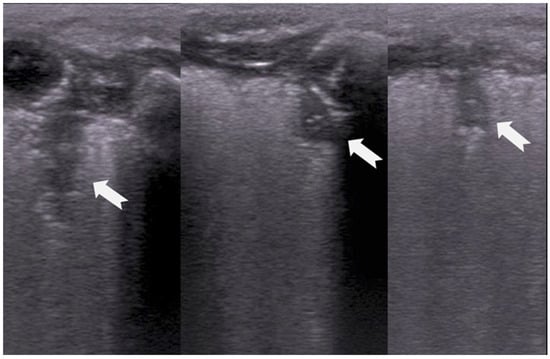

B-lines are vertical reverberation-like hyperechoic artifacts seen during LUS imaging which originate from the pleural line and extend to the bottom of the imaging field without fading in intensity (Figure 2a). B-line artifacts move in synchrony with lung sliding and intersect horizontal A-lines, effectively obscuring them. Their presence is typically associated with fluid accumulation in the alveoli or interstitial space, and they are commonly referred to as ultrasound lung comets. However, B-lines are frequently observed in neonates and can appear as a normal finding within the first 24 to 48 h after birth [13,14,17]. During LUS imaging, identification of up to two B-lines at the lung base is considered to be normal, while the presence of three or more B-lines between the intercostal space in a single view is considered significant and indicative of an underlying pathology. If multiple B-lines are identified by LUS, then the patient likely suffers from interstitial syndrome. When the air content in the lungs decreases, the number of lines tends to increase, because of the associated increase in lung density. Moreover, when the identified B-lines are confluent, this is an indication that the alveoli are filled with sub-pleural fluid. When interstitial edema is present, the presence or absence of B-lines can guide the administration of fluids [16,17,18,19]. However, it should be noted that B-lines are absent in the aforementioned pneumothorax.

Figure 2.

B-lines: Vertical reverberation-like hyperechoic artifacts originate from the pleural line and extend to the bottom of the image (a). This artifact could be normal (<3 in an intercostal space) or abnormal when are more than three, multiple or coalescent B-lines (b).

According to severity of the lung or interstitial pathology, B-lines may be solitary, few, multiple or even coalescent (Figure 2b), resulting in three imaging patterns associated with increasing severity: black lung, black and white lung, or white lung (Figure 3) [20,21].